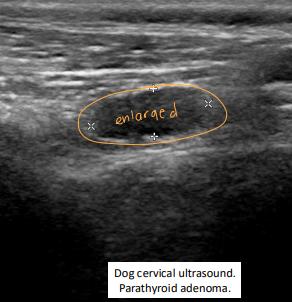

Primary Hyperparathyroidism

Et: hypercalcemia

Sig: older dogs 4-17y, parathyroid adenoma → benign fnx

Cs: PU/PD, weakness, Incontinence, vomiting, diarrhea, shivering, Lower UTI signs→ stones, dilute urine(1.004-1.037)

soft tissue mineralization if Ca × P product >70

Dt: ↑ ionized Ca + PTH, low P, PTHrP is negative

Tx: parathyroidectomy, RF ablation, ethanol ablation

Post-tx: risk of hypocalcemia w/in 5 days → calcitriol + Ca